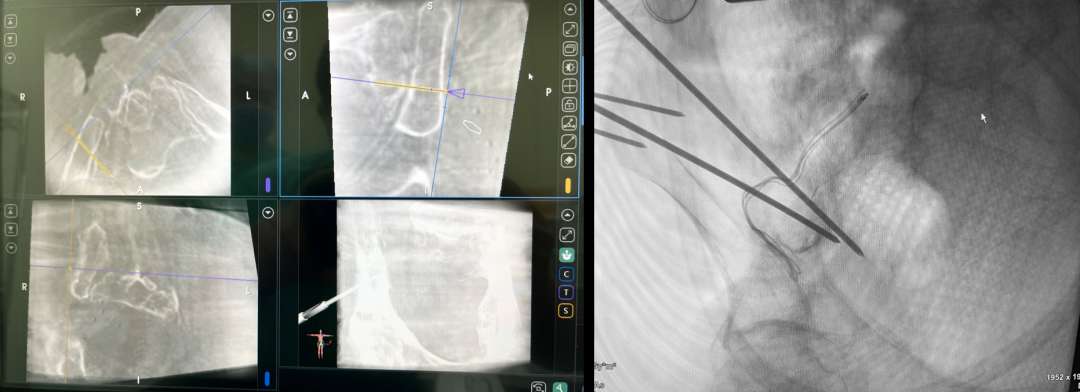

这一手术方案得到了手外科主任陈山林教授和手术室麻醉科医护团队的大力支持。术中由王树锋、李文军主任医师娴熟地经臀大肌显露坐骨大孔,由殷耀斌副主任医师与医工团队默契地进行导航机器人的规划。术中依据患者骶髂关节的形态,在骨科机器人的辅助下分别在坐骨大孔周围的髂骨和骶骨后方皮质上置入截骨规划的导针,依据导针的定位与方向,顺利地进行了精准的个性化截骨,成功显露了深方重要的神经血管束,减少了出血,避免了多次截骨导致骨块难以复位固定或误伤深方器官的风险,为后续神经移位修复手术提供重要保障。

术中王树锋主任医师(左一)与李文军主任医师(右一)在骨科机器人的辅助下精准地置入导针。

术中导航辅助准确定位形态不规则的坐骨大孔,机器人辅助精准置入导针。